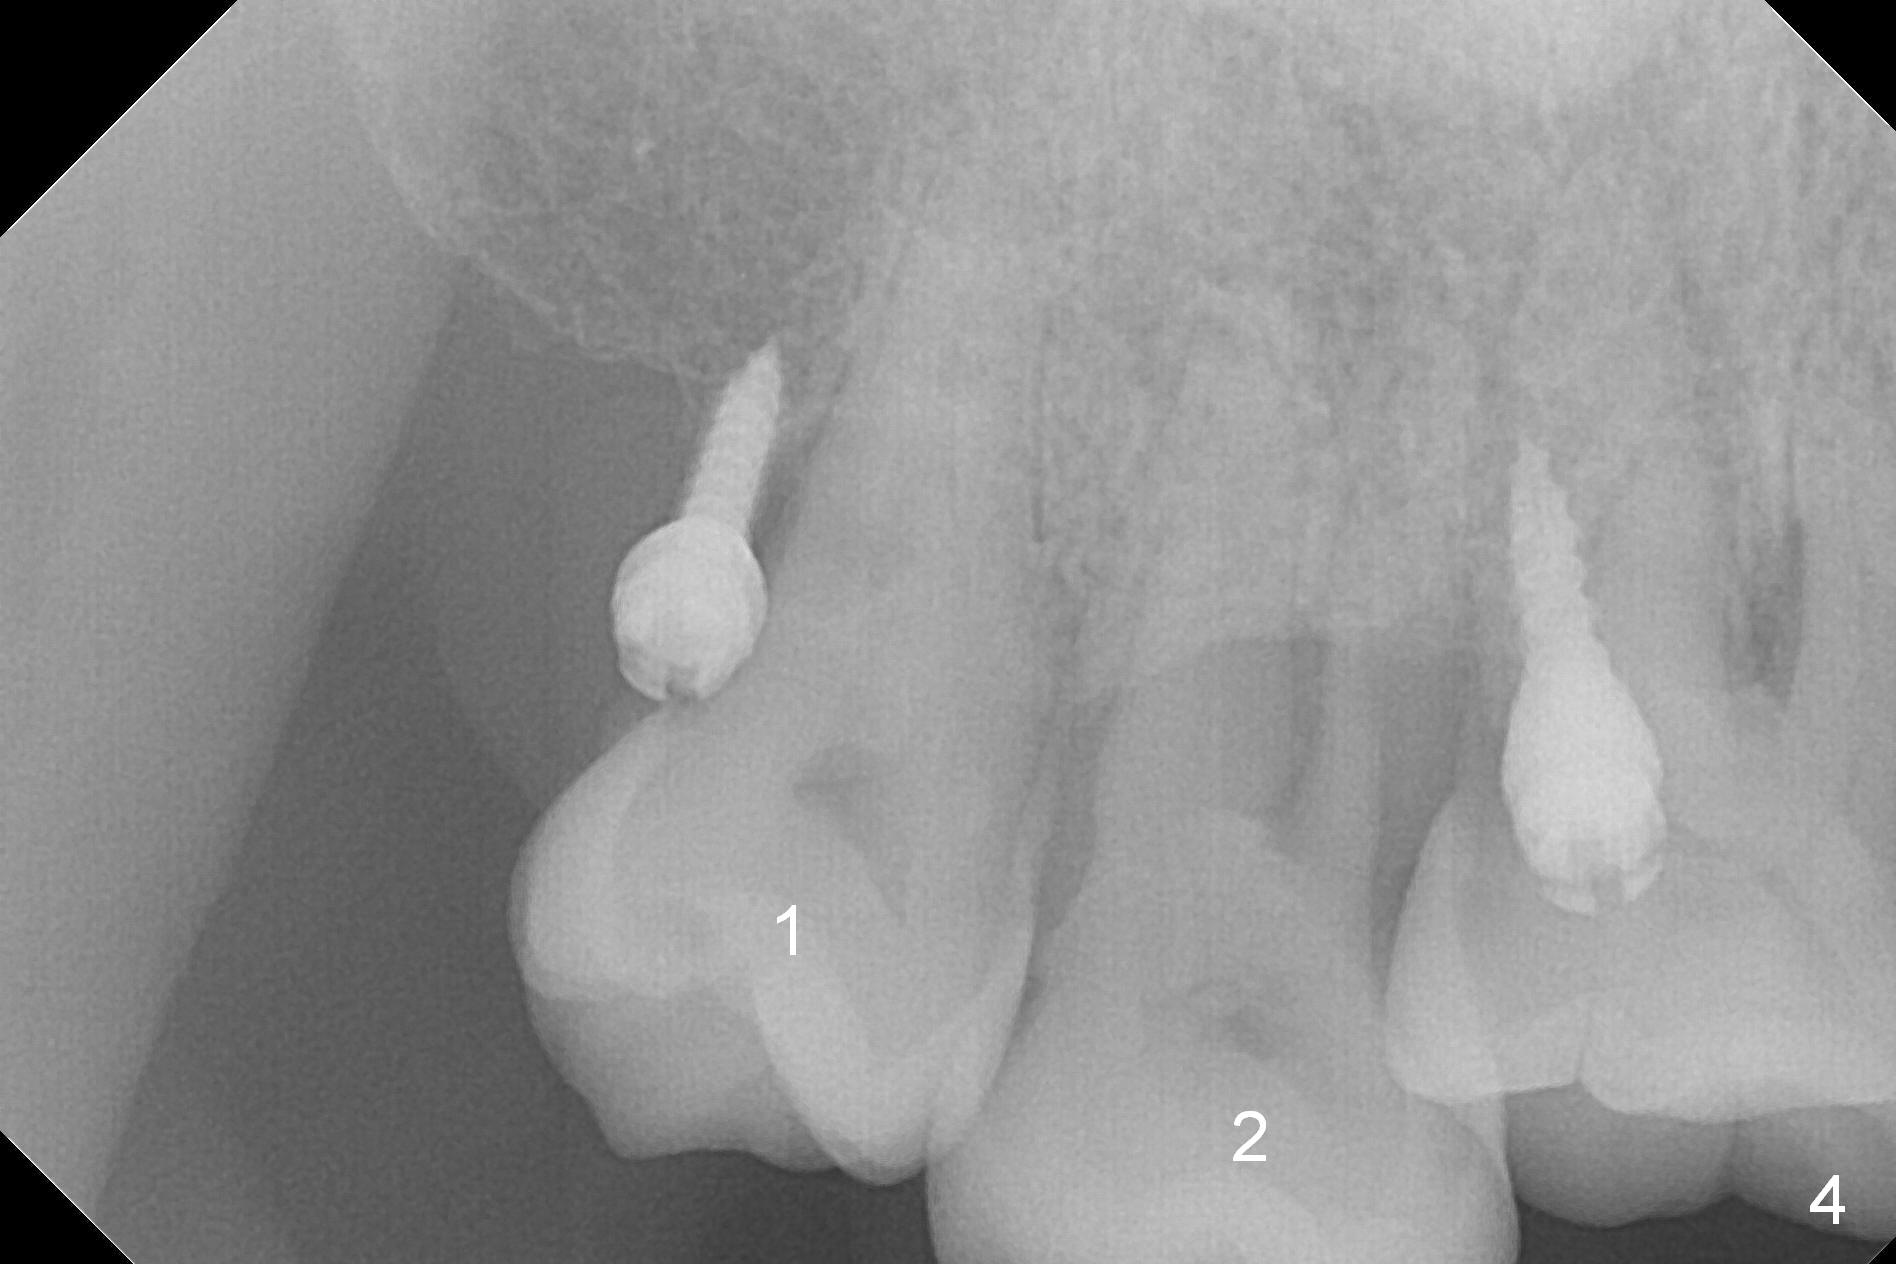

Two days post #31 implant placement, the patient returns for orthodontic intrusion of the tooth #2 with mini-implants (Fig.1). The palatal cusps have been trimmed (Fig.2 ^), since they almost contact a healing abutment at #31(*, Fig.3). Two mini-implants are to be placed mesiobuccal and distopalatal to the affected tooth. After minimal injection of Lidocaine, a 1.6x6 mm Tomas implant is placed in full length mesially (Fig.4), while the other (1.6x8 mm) half way (Fig.4). Following change in implant site mesially (Fig.6 >), the implant is half inserted (Fig.5). It appears that the tip of the distal implant is toward the tooth #1 (Fig.5). After withdrawing the implant partially, it is re-directed to apparently ideal trajectory (Fig.7). Ideally the mesial implant (Fig.8) should have been placed partially initially (Fig.4,5,7) so that the trajectory could have been able to be changed.

The buccal implant becomes loose in 2-3 months. When the wound heals (Fig.9 <), a 1.6x`10 mm implant is placed with the help of PAs for trajectory (Fig.10,11) and in the nonkeratinized gingiva (higher, the crestal bone may have been traumatized by previous implant placement, Fig.12). Two months later, the tooth #2 is partially intruded (Fig.13). A provisional (Fig.14 P) is fabricated in the osteointegrated implant at #31 with supraocclusion so that the remaining dentition has no occlusal contact (*). The periodontally compromised tooth #2 becomes in buccoversion in 2 months. The provisional is removed, while a lingual button is placed in the buccal surface of the tooth #2 (Fig.15). With power chain attached to the lingual mini-implant, the tooth #2 is lingualized in 2 months. The provisional and the implants are reused for final intrusion (Fig.16). The treatment is nearly 11 months. The buccal implant, although placed in the movable mucosa, remains stable and healthy (Fig.17). The tooth #1, as a guiding plane (to prevent #2 from distalization during intrusion), is not extracted after intrusion is completed.